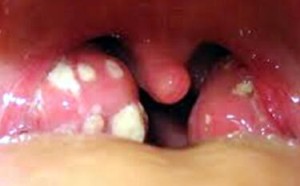

扁桃体反复发炎会对孩子的健康造成哪些危害?

孩子得了化脓性扁桃体炎别急着输液 有些情况可以药物治疗

24752017/6/26 16:49:21